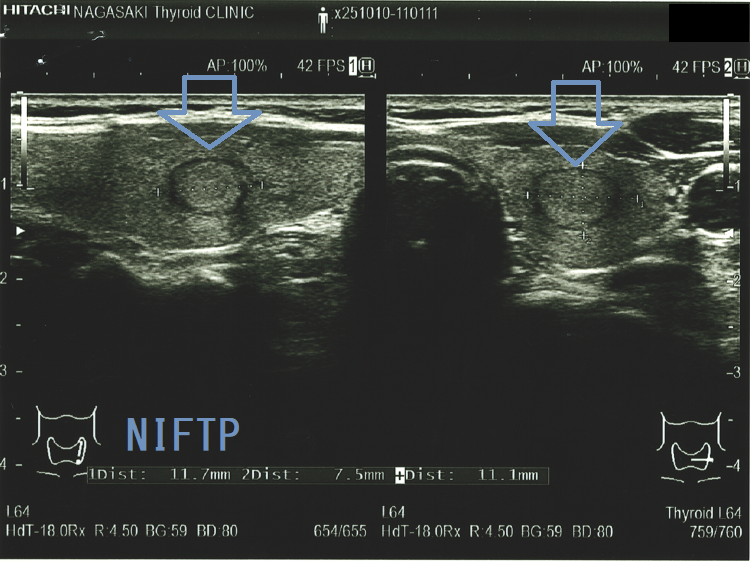

(a)Non-invasive follicular thyroid neoplasm with papillary-like nuclear features (NIFTP) 超音波(エコー)画像;見かけは濾胞型甲状腺乳頭癌、甲状腺濾胞癌、腺腫様結節と鑑別できまない

Non-invasive follicular thyroid neoplasm with papillary-like nuclear features (NIFTP)の超音波(エコー)所見は、

- 被膜が存在(被膜のない場合もある)

- 充実性、等エコーが多い

- 砂粒状石灰化を認めない

で、濾胞型甲状腺乳頭癌、濾胞性腫瘍(良性濾胞腺腫 、甲状腺濾胞癌)と超音波(エコー)所見にて鑑別できません。砂粒状石灰化のない濾胞型甲状腺乳頭癌なんて普通に存在します。NIFTPの60.1%は悪性を疑う所見が無いとされます[Endocrine. 2021 Jul;73(1):131-140.]。